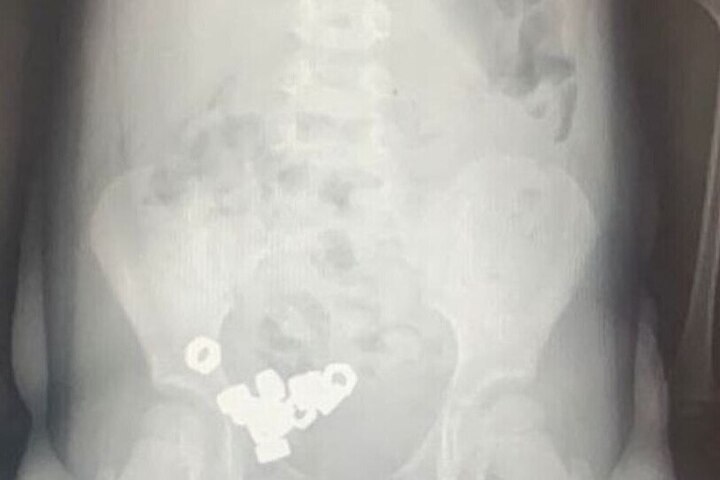

В Воронеже трехлетний ребенок проглотил 16 гаек. Малыша оперативно доставили в областную детскую больницу №2, где ему оказали необходимую помощь. Информацию об инциденте предоставил региональный Минздрав.

Как сообщили родители юного пациента, он мог проглотить посторонние предметы. На момент врачебного осмотра симптомы отсутствовали, но рентген подтвердил наличие небольших гаек в желудочно-кишечном тракте ребенка.

Малыша госпитализировали для наблюдения и лечения. Врачи выбрали консервативный подход, поскольку гайки не были магнетическими или инертными. Лечение включало специальную диету, покой, регулярный мониторинг стула и динамическую рентгенографию.

На третий день все гайки вышли естественным путем, после чего ребенка выписали из больницы.